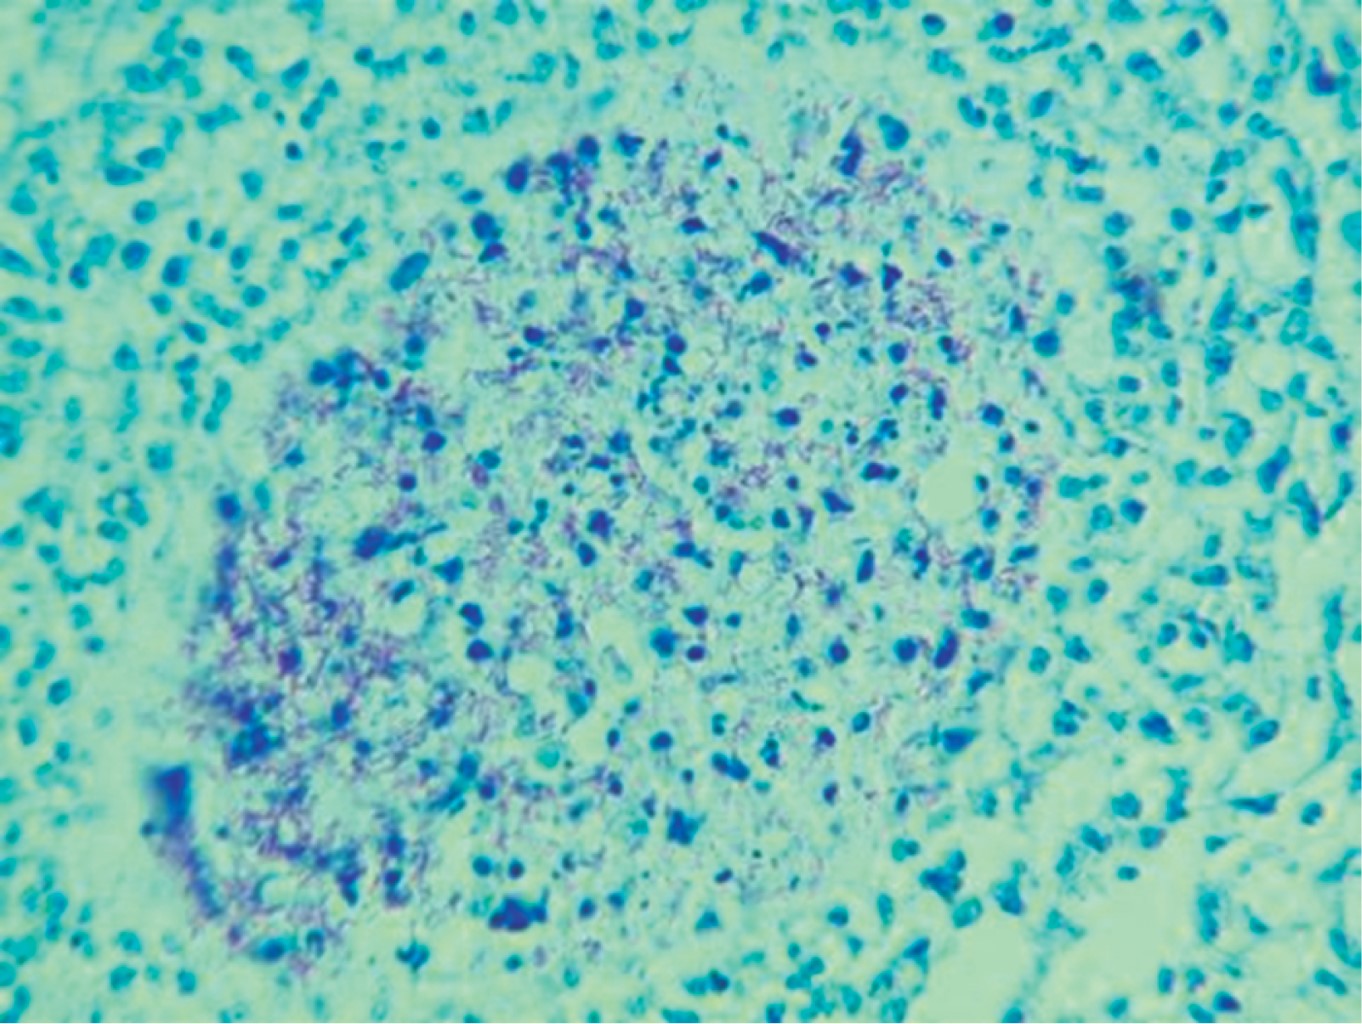

We present the case of 33-year-old male with multiple risky sexual partners. He was treated by a private physician, who performed an ultrasound and clinically corroborated the diagnosis of orchi-epididymitis, for which he received antibiotic treatment with no improvement. Three weeks later he sought a second opinion; a new ultrasonography scan was performed, and the diagnosis of orchi-epididymitis was confirmed, so he was treated again with antibiotics without remission of symptoms. One month later he experienced left testicular enlargement (approximately 10 × 8 cm), weight loss, asthenia and adynamic, so while seeking a third opinion, he went to a public hospital where he underwent a left orchiectomy on suspicion of seminoma, being discharged after 48 hours. That same day he presented constant pain, inability to pass gases and to evacuate, progressive abdominal distention, nausea and vomiting of gastro-alimentary content, so he requested a fourth opinion and underwent a laparoscopy procedure for intestinal occlusion. Multiple implants were found throughout the small intestine as well as retroperitoneal lymph node growth that caused intestinal occlusion at the level of the Treitz angle. A derivative gastrostomy and jejunostomy for feeding were performed, and lymph node biopsies were taken. His evolution was torpid, and he died on the third postoperative day. Two days after his death, a histopathological report of both surgeries was received, which concluded testicular tuberculosis (Figures 1 and 2) and a report of the ELISA test for HIV was received, which was positive.

Figure 1